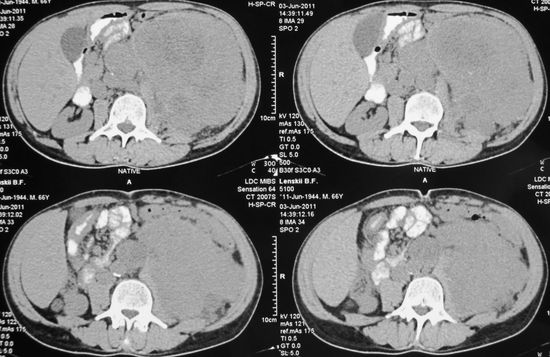

Опухоль левой почки

Опухоль левой почки, выпячивающая переднюю брюшную стенку